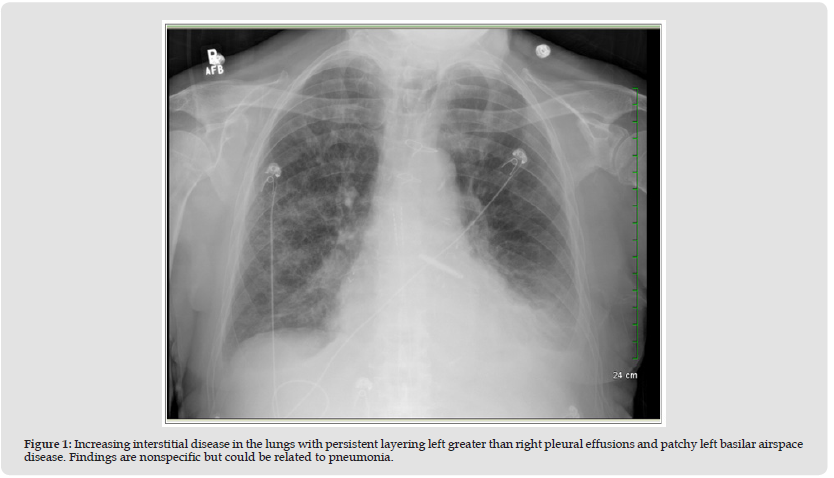

Echocardiography revealed Ejection Fraction (EF) is 60 to 65% with no diastolic RV (Right ventricle) collapse along with moderate to large pericardial effusion without tamponade. Since patient has elevated ESR (Erythrocyte Sedimentation Rate) and CRP (C-Reactive Protein) start colchicine 0.6 mg twice daily is started for his pericardial inflammation. Cardiothoracic surgery is consulted for consideration of pericardial window and it was performed on 08/03/2025. Over 200cc sero-sanguineous fluid from the pericardium. The fluid was collected and sent for the usual analysis and cultures. Pericardial drain was attached to Pleur-evac suction. Patient tolerated procedure well and was transported to CCU in stable condition. Broad spectrum antibiotics were started based awaiting the culture results. Overnight another 90cc of fluid was drained from the pericardial drain. Following the procedure his shortness of breath decreased considerably and he was discharged to his nursing facility (Figure 1).